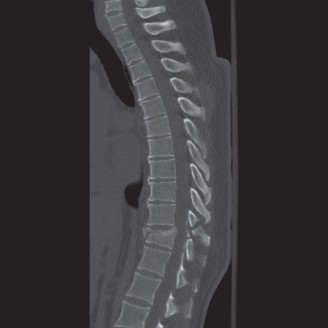

Radiographic and Computed Tomography Evaluation

Initial trauma radiographs demonstrated a loss of anterior and middle column height at L1, with a focal kyphotic deformity. However, plain films are vastly insufficient for definitive surgical planning in thoracolumbar trauma. A high-resolution, fine-cut Computed Tomography (CT) scan of the entire spine was obtained. The CT images confirmed an L1 burst fracture with severe comminution of the vertebral body. Sagittal and axial reconstructions revealed 50% canal compromise secondary to a large retropulsed bone fragment originating from the posterosuperior aspect of the L1 vertebral body. Furthermore, the CT demonstrated 25 degrees of segmental kyphosis measured from the superior endplate of T12 to the inferior endplate of L1.

Therefore, the gold standard, definitive treatment for this specific injury pattern is an instrumented posterior fusion. By placing pedicle screws above and below the fractured level, we can utilize ligamentotaxis to partially reduce the retropulsed fragment, restore vertebral height, and rigidly recreate the posterior tension band. This is where the concept of preventing Adjacent Segment Degeneration (ASD) enters our operative planning. If we fuse this patient in 25 degrees of segmental kyphosis, we will create a flatback deformity. The adjacent unfused segments (particularly L2-L3 and L3-L4) will be forced into hyperlordosis to compensate, leading to accelerated facet arthropathy, disc degeneration, and eventual adjacent segment failure. Our surgical goal is not just stabilization, but the meticulous restoration of regional sagittal alignment.

The final, critical step is rod contouring and reduction. To prevent future Adjacent Segment Degeneration, the titanium rods must be contoured to match the patient's ideal pelvic incidence and lumbar lordosis. The rods are seated into the proximal screws. Using reduction towers and careful cantilever forces, the rods are seated into the distal screws. This maneuver actively corrects the 25-degree kyphotic deformity, restoring normal sagittal alignment. The construct is cross-linked if necessary, and a robust posterolateral decortication and bone grafting (using local autograft from the laminectomy and allograft) is performed to ensure a solid arthrodesis.

Long-term follow-up at 6 weeks, 3 months, 6 months, and 1 year will focus on assessing fusion mass consolidation and monitoring for any signs of hardware failure. More importantly, long-term surveillance (2 to 5 years post-op) will focus on the adjacent segments. By having meticulously restored the sagittal vertical axis (SVA) and regional lordosis during the index procedure, we have minimized the abnormal shear and compressive forces on the T10-T11 and L3-L4 discs, drastically reducing the patient's risk of developing Adjacent Segment Degeneration requiring revision surgery.